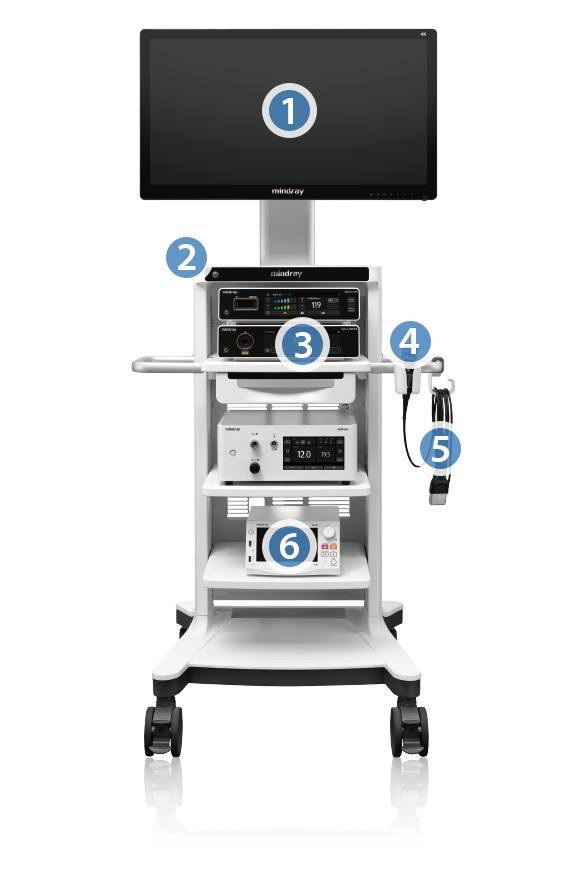

1

Monitor 3D 4K de 32/55 pulgadas

2

Carro Master con interruptor de un botĂłn

Inicie todos los dispositivos del carro con un solo toque

3

Fuente de luz con luz blanca/fluorescencia

Control de intensidad automatico en todas series

4

Cabezal de cĂĄmara con luz blanca/fluorescencia

Varias distancias focales disponibles

Peso del cabezal de cĂĄmara con luz blanca: 190g

Peso del cabezal de cĂĄmara con fluorescencia: 240g

5

Endoscopio rĂgido de 10/5 mm

Disponibles endoscopios rĂgidos de fluorescencia de varias especificaciones

6

Videograbador digital médico

Acceda a la grabaciĂłn simultĂĄnea del sistema PACS del hospital de dos fuentes de se?al disponibles